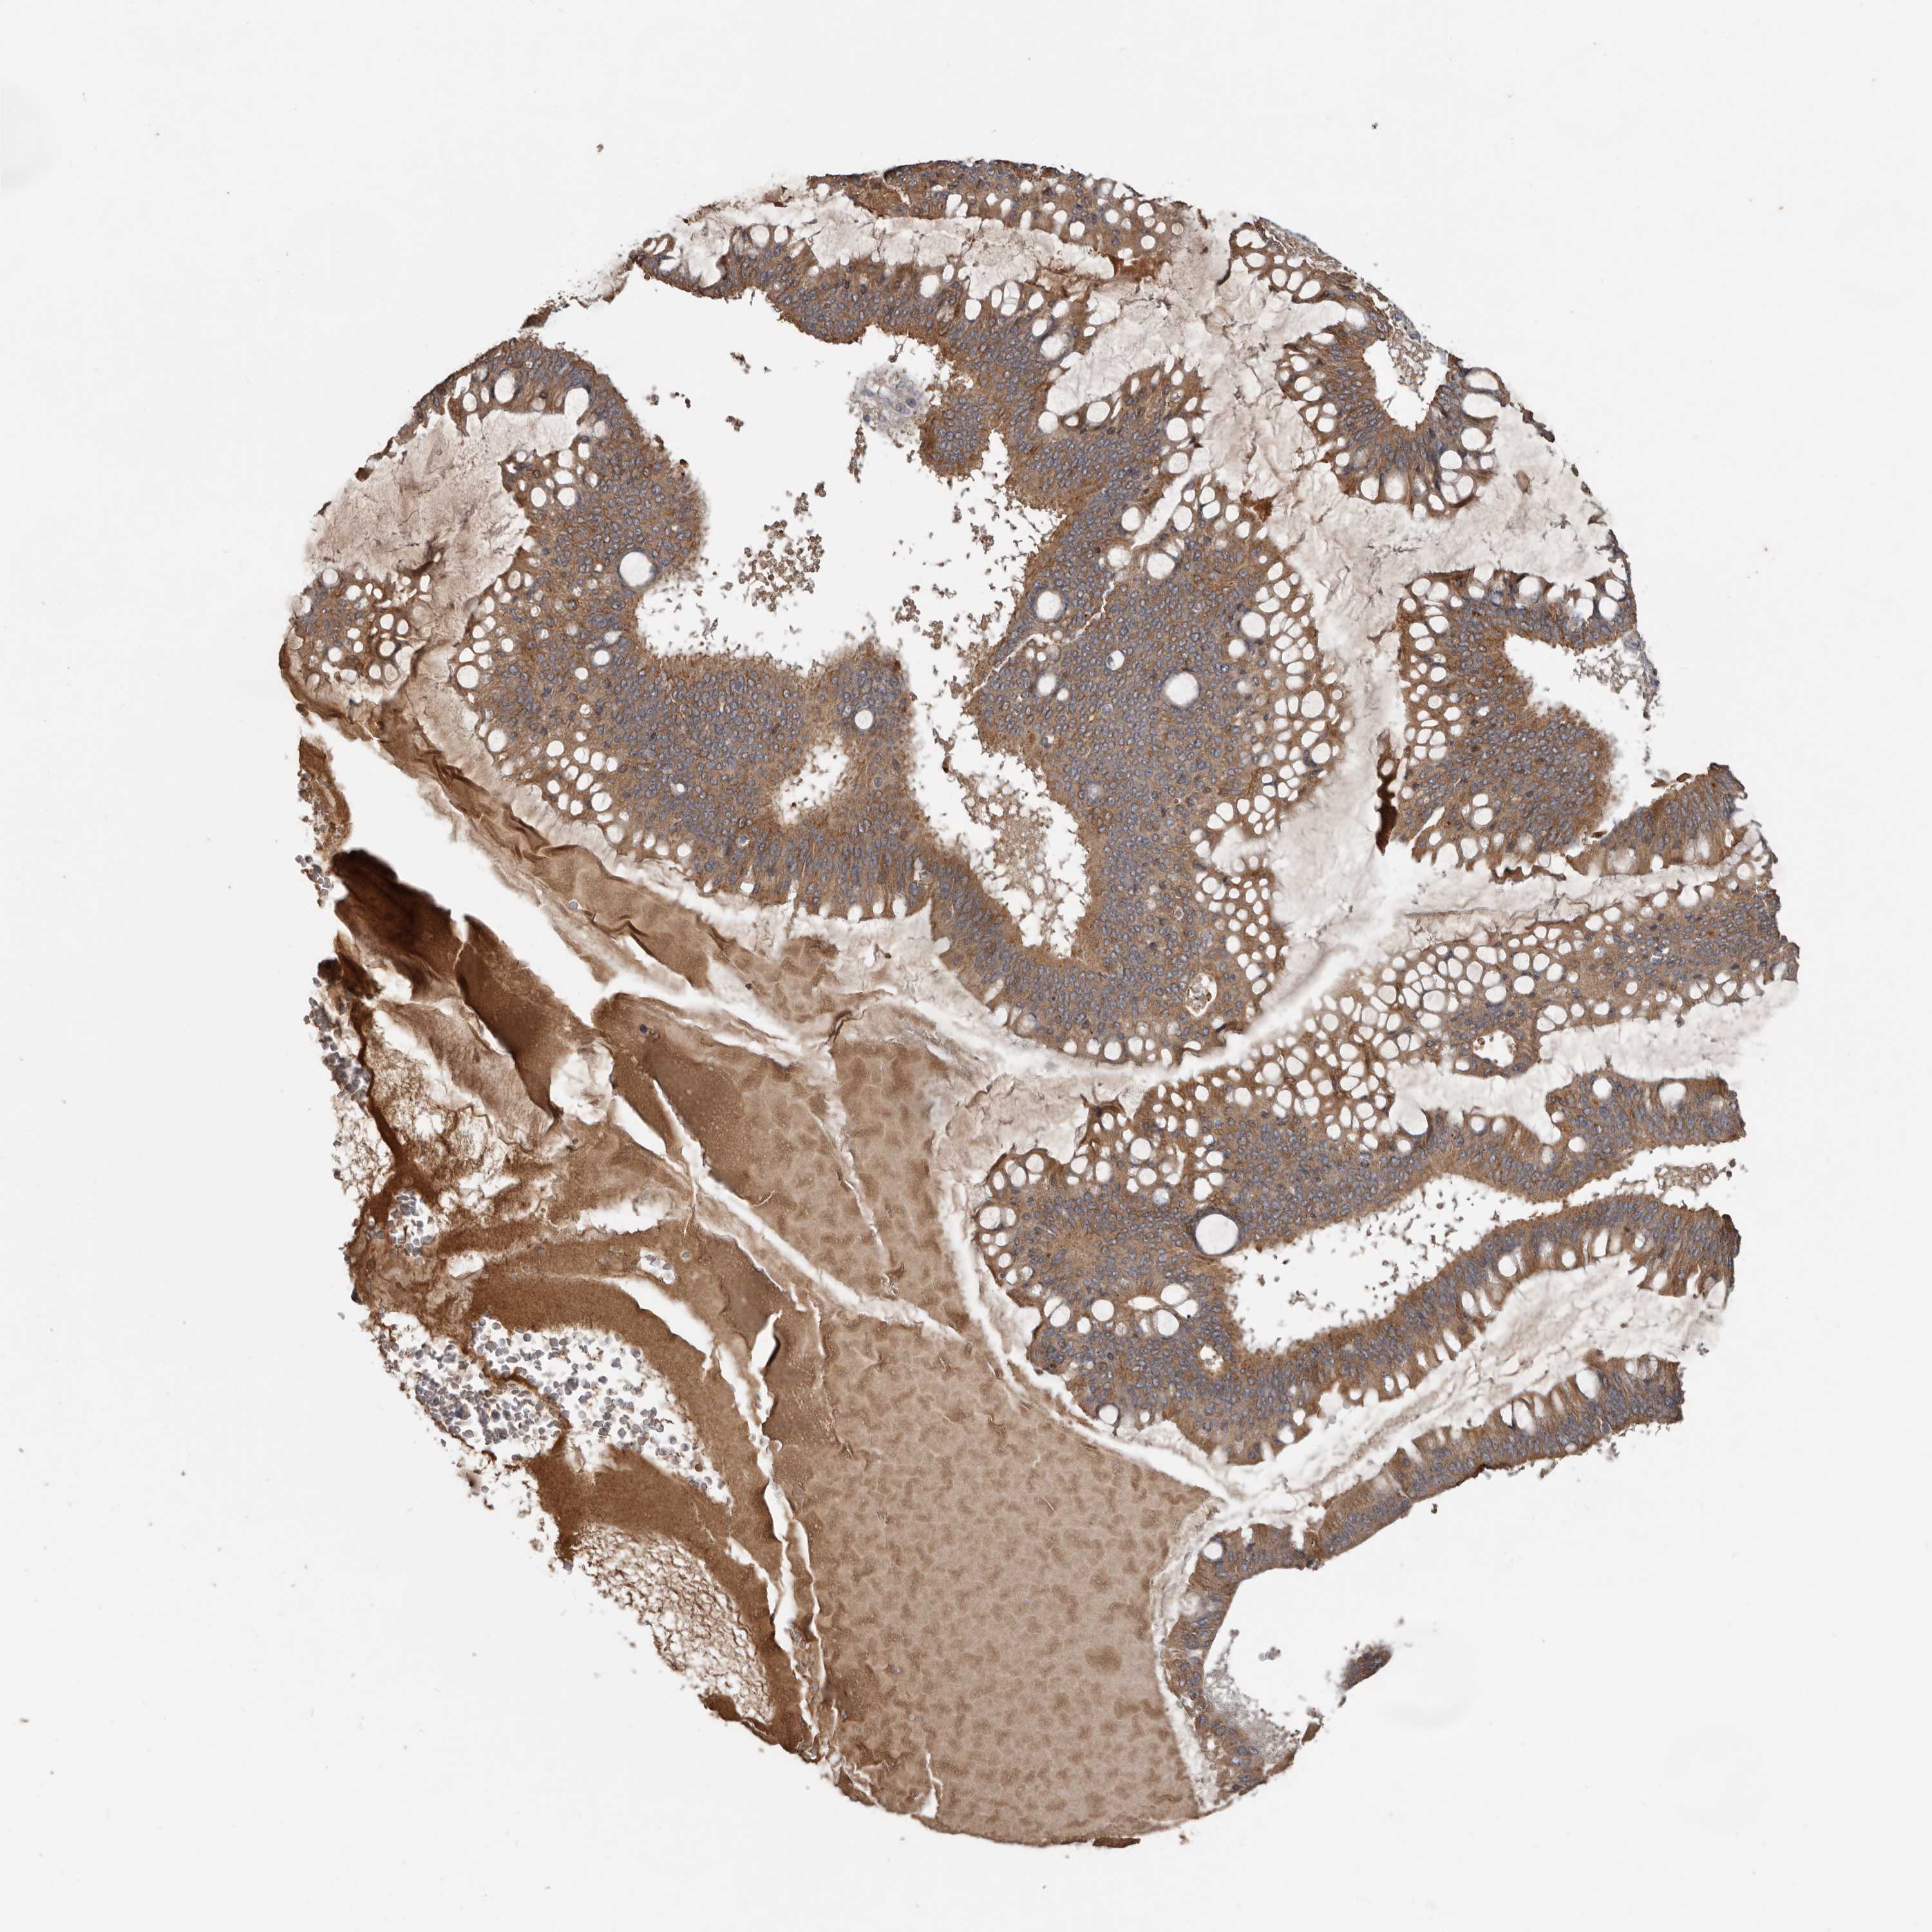

OVARIAN CANCER - Protein expressioni

A mouse-over function shows sample information and annotation data. Click on an image to view it in a full screen mode. Samples can be filtered based on level of antibody staining by selecting one or several of the following categories: high, medium, low and not detected. The assay and annotation is described here.

Note that samples used for immunohistochemistry by the Human Protein Atlas do not correspond to samples in the TCGA dataset.

Antibody stainingi

Antibody staining in the annotated cell types in the current human tissue is reported as not detected, low, medium, or high, based on conventional immunohistochemistry profiling in selected tissues. This score is based on the combination of the staining intensity and fraction of stained cells.

Each image is clickable and will lead to virtual microscopy that enables deeper exploration of all samples and also displays staining intensity scores, fraction scores and subcellular localization as well as patient and tissue information for each sample.

Antibody HPA027895

Staining

High

Medium

Low

Not detected

Intensity

Strong

Moderate

Weak

Negative

Quantity

>75%

75%-25%

<25%

None

Location

Nuclear

Cytoplasmic/membranous

Cytoplasmic/membranous,nuclear

Cystadenocarcinoma, serous, NOS

Carcinoma, endometroid

Cystadenocarcinoma, mucinous, NOS

Carcinoma, NOS